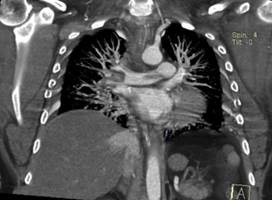

Bajo ese contexto sospechando TEP para confirmar el diagnóstico se realiza Angio-tc de vasos pulmonares (Fig.2 ), que mostro falta de captación de medio de contraste en arteria pulmonar derecha , en cuanto a los exámenes de laboratorio lo más relevante fue troponina 4,7630 u/l , dímero-d 54490,00 ng/ml , ferritina 27300,00 ng/ml. Se procedió a iniciar tratamiento fibrinolítico, que al no contar con r-tpa (alteplase) se usó estreptoquinasa 1.500.000 UI  que fueron administradas de forma intravenosa en una hora, seguida de anticoagulación con enoxaparina, después se evidencio mejoría en la oxigenación y hemodinámica, a las 24 horas se realiza nuevo rastreo ecocardiográfico (Fig. 3) en el cual existe mejoría de función ventricular derecha.

Figura 2. Angiotomografía pulmonar. Se evidencia no captación del medio de contraste en la arteria pulmonar derecha.